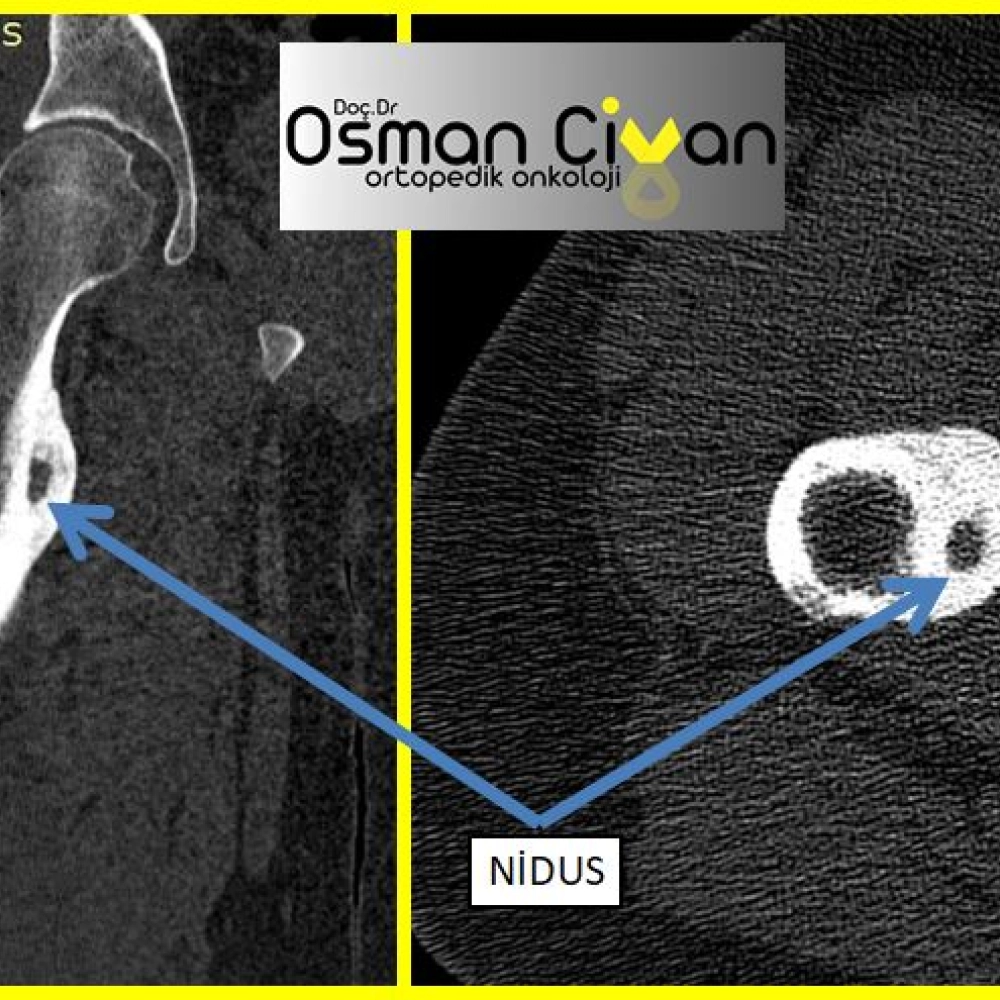

Osteoid Osteoma

Kemik Tümörleri / Osteoid Osteoma

Osteoid Osteoma Nedir? Genellikle genç erişkinlerde ve çocuklarda görülen iyi huylu kemik tümörlerinden...